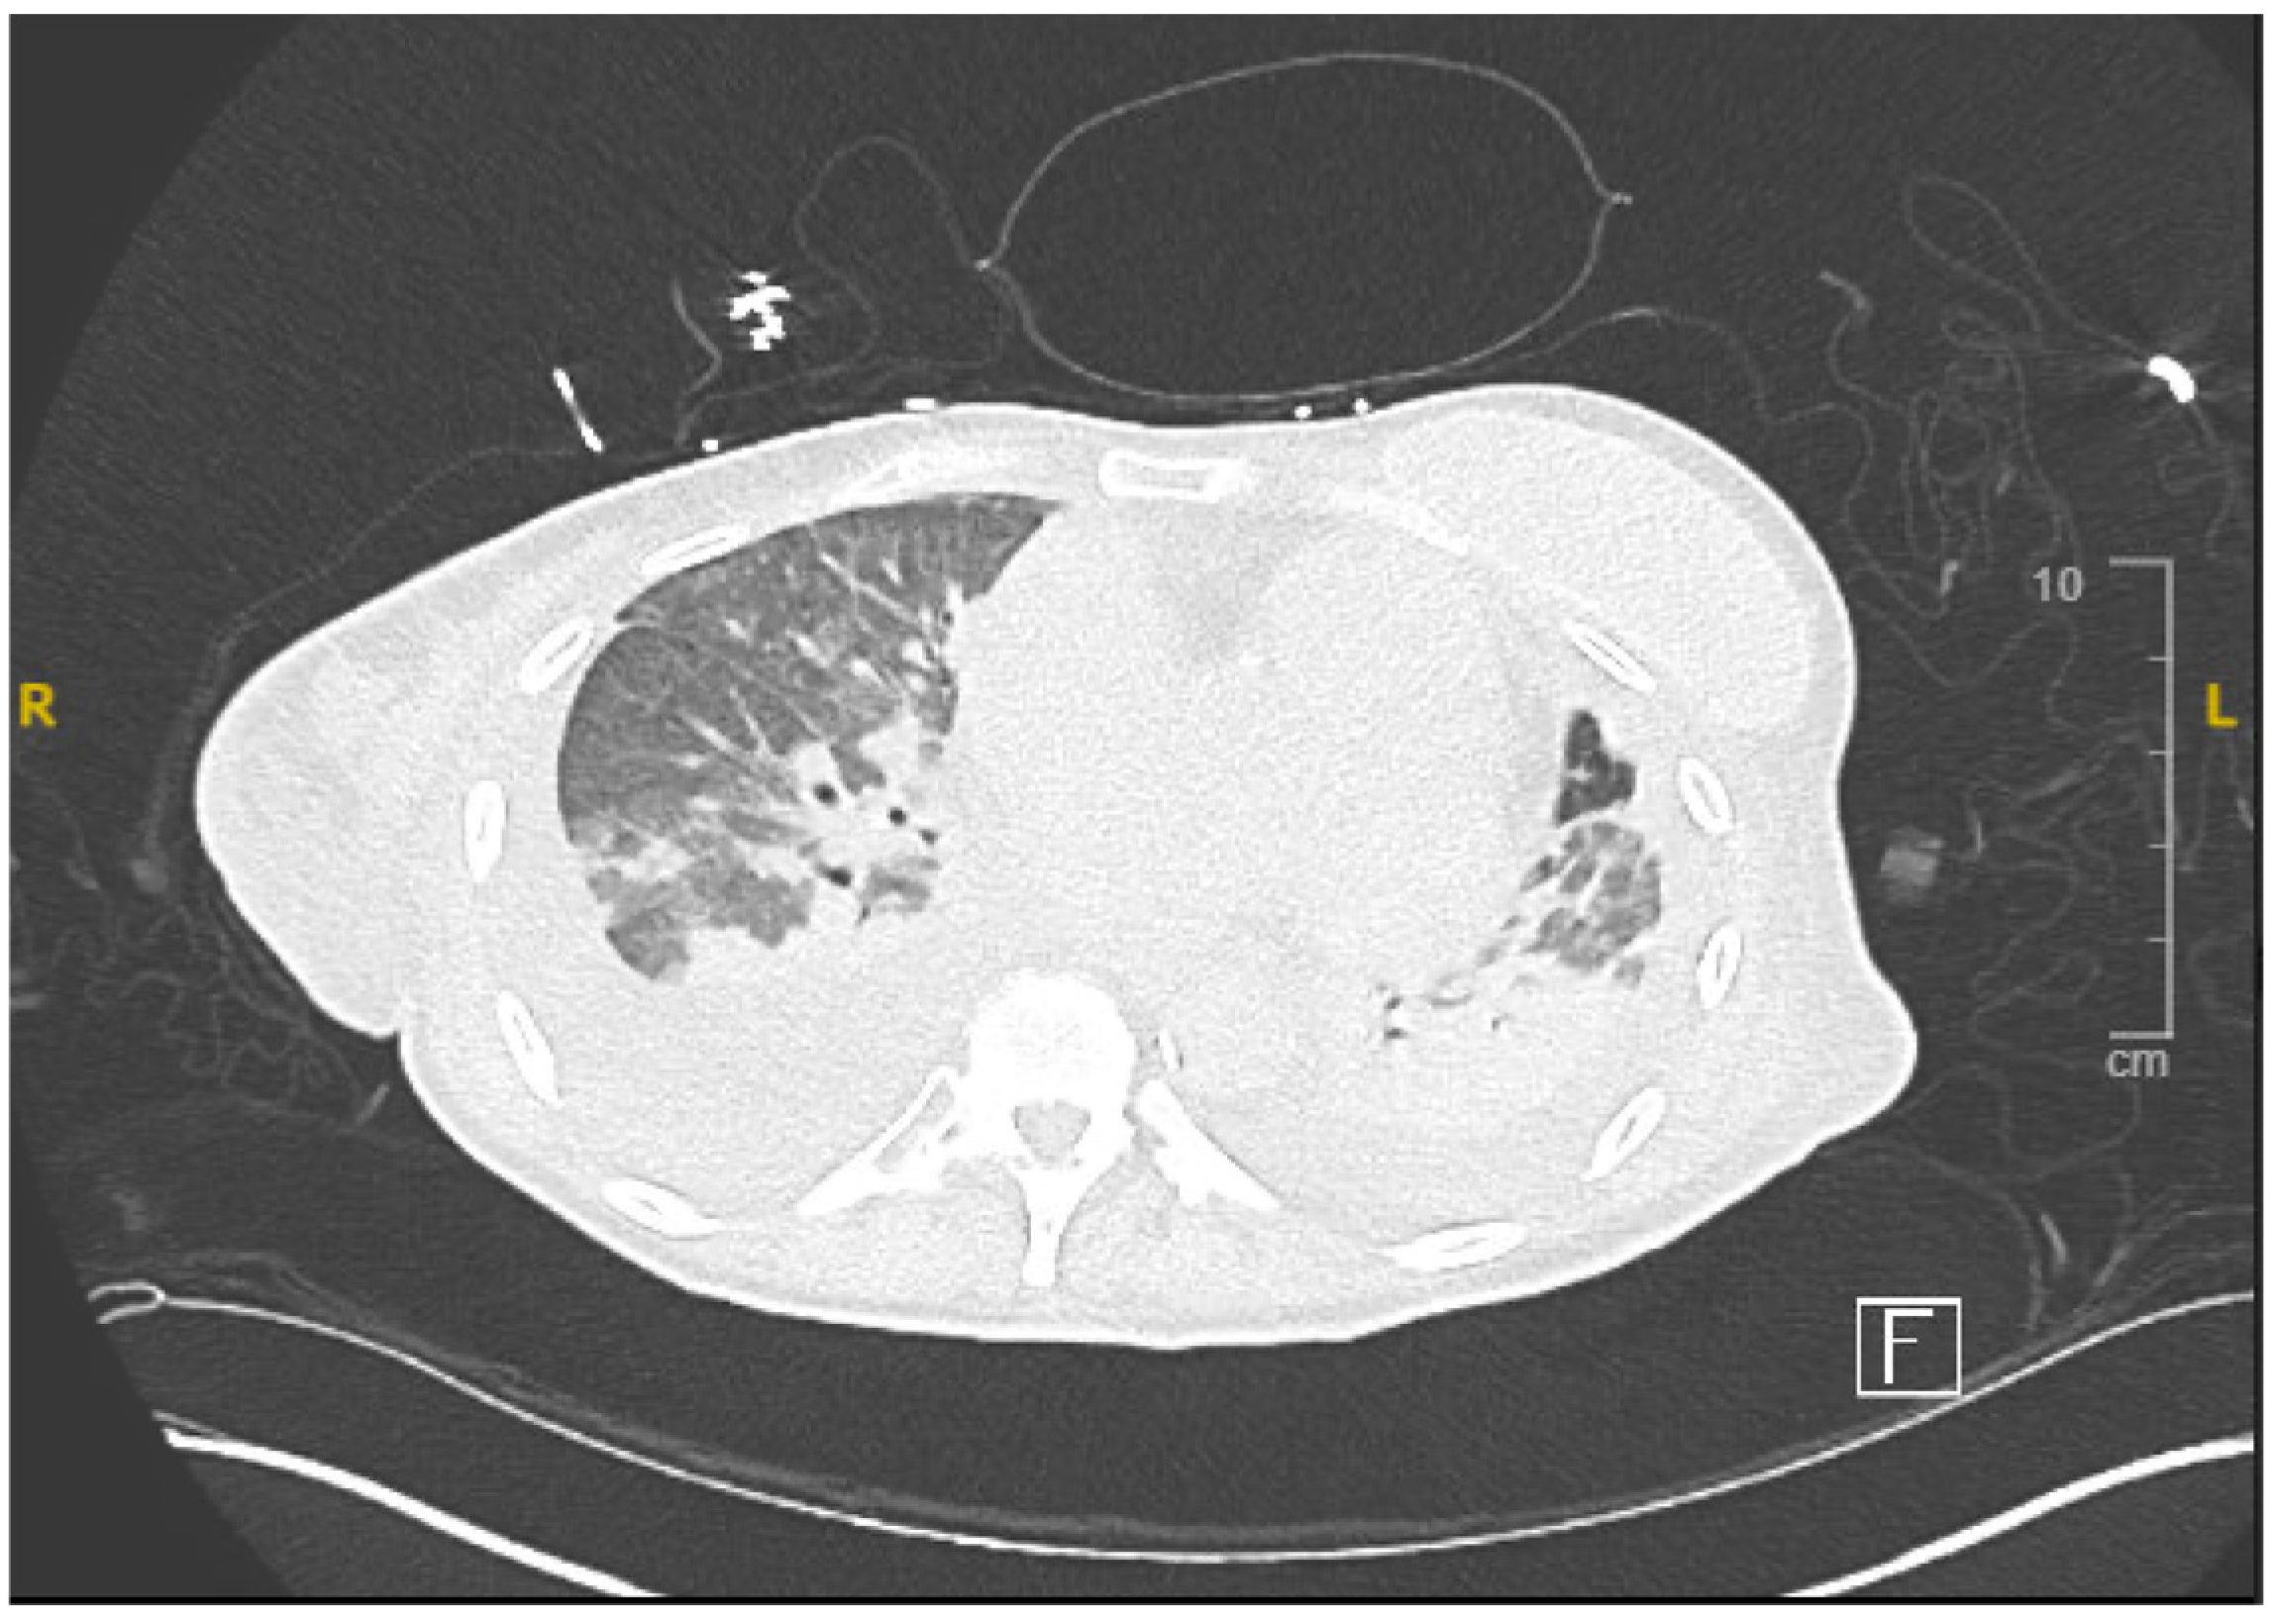

The electrocardiogram (ECG) indicated normal sinus rhythm, with the presence of right axis deviation and left atrial enlargement (Figure 1). The pro-brain natriuretic peptide (BNP) was notably elevated at 17,000. Both rheumatological and immunological evaluations were negative. Infectious disease assessment was notable for reactivity on the Hepatitis B viral panel, while the HIV test returned negative. The chest X-ray revealed pulmonary edema with a left-sided pleural effusion (Figure 2). A computerized tomography (CT) pulmonary angiogram did not show any evidence of pulmonary emboli (PE), but it did indicate diffuse bilateral ground-glass opacities consistent with pulmonary edema, as well as enlargement of the pulmonary arteries and cardiomegaly (Figure 3). Clinical suspicion for pneumonia was deemed unlikely, as there was an absence of an elevated white blood cell count and C-reactive protein.

Figure 3. Computed tomography demonstrating bilateral ground glass opacities.